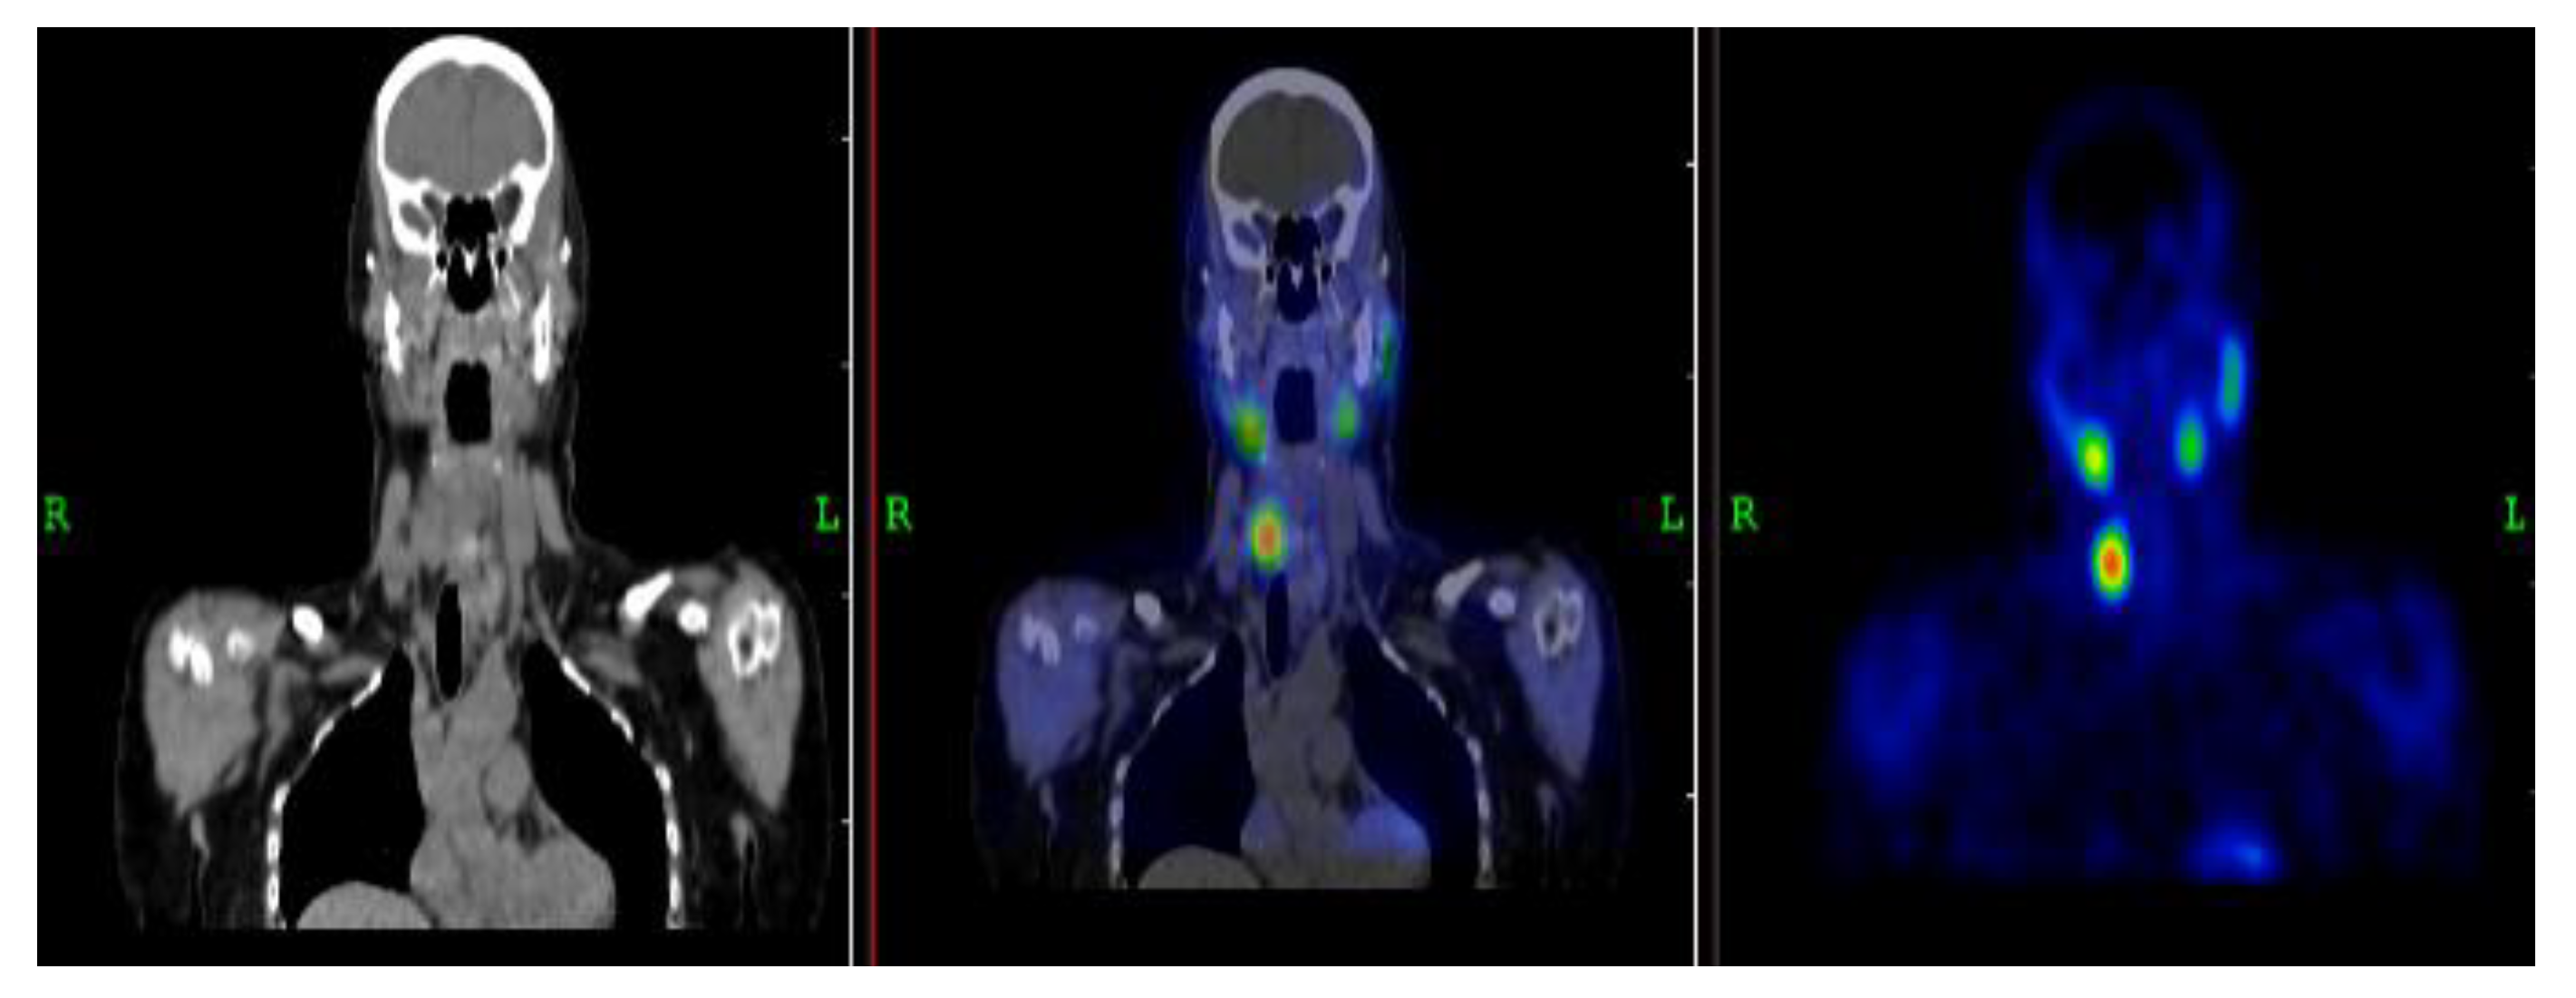

3.2.2. Representative Clinical Case 2